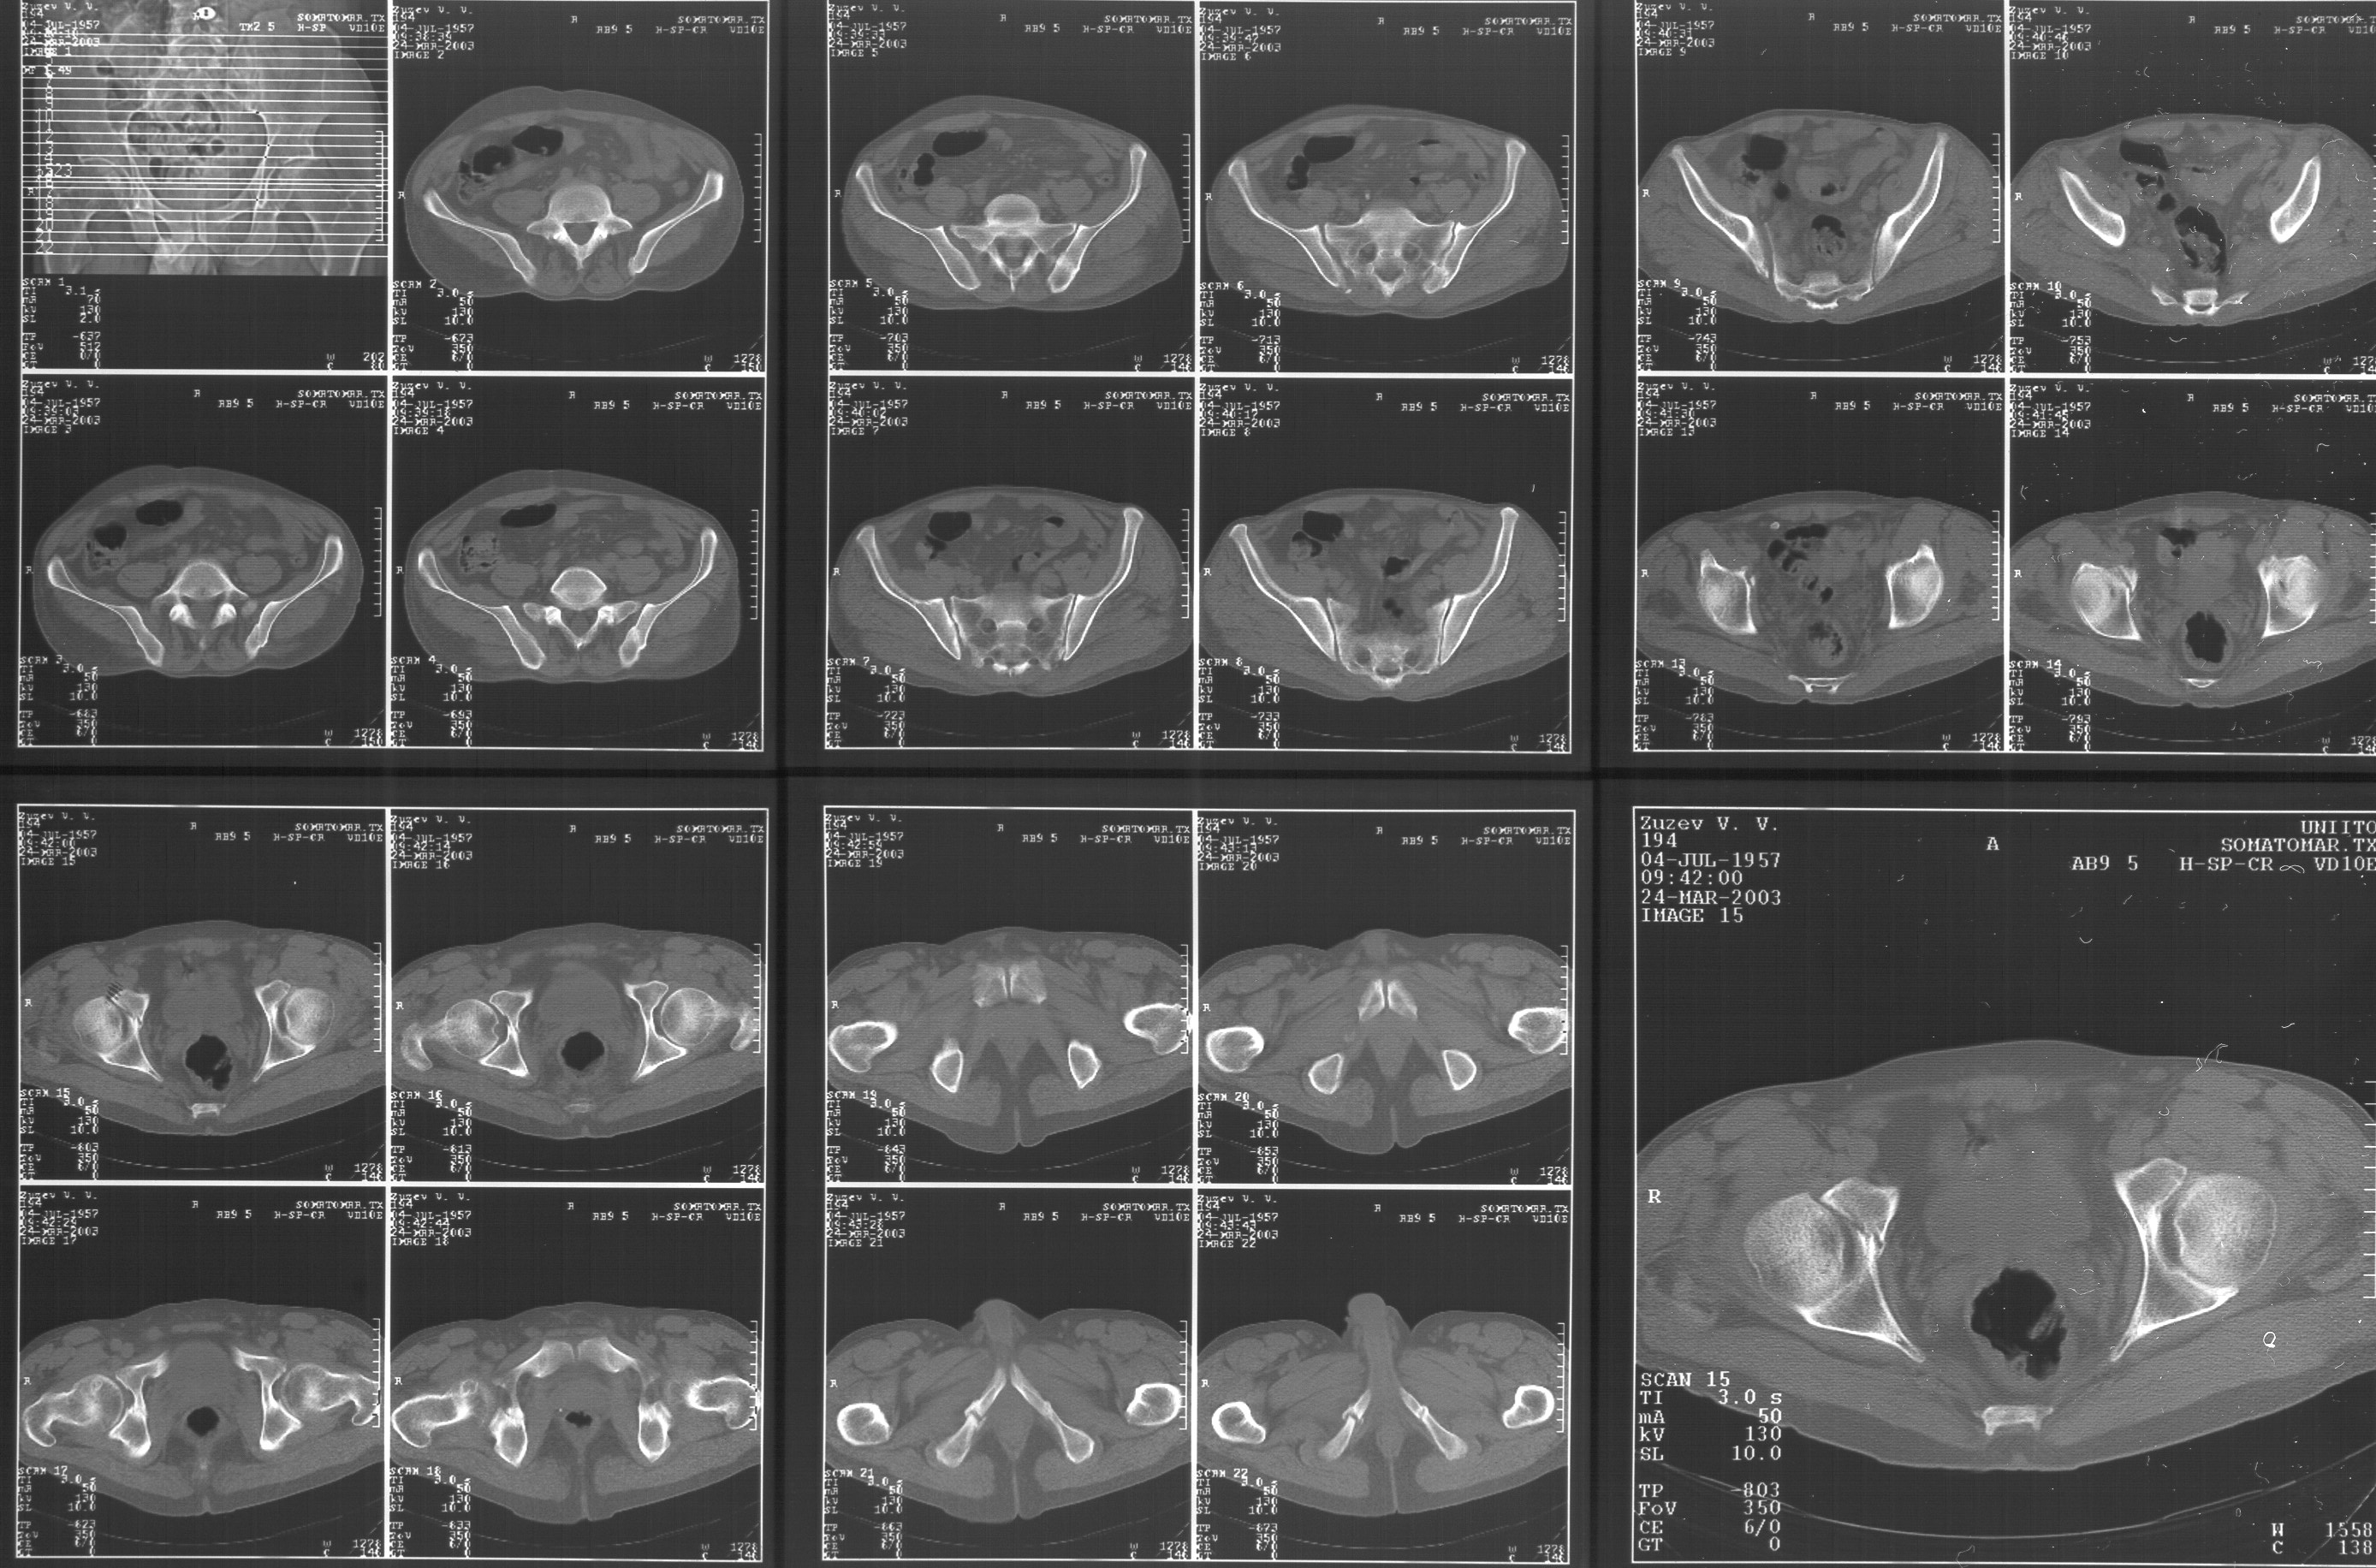

Прилагаю свежую КТ таза.

Картинки см. ниже, левая - с экранным разрешением, вторая - полноразмерная, ~900 кб.

КТ в экранном разрешении

Полноразмрная картинка, около 900 кб

Based on the CT images you provided, he appears to have a nonunion of the the right ischium, which would explain his symptoms. General principles of treatment of hypertrophic (which this appears to be) nonunions suggest rigid fixation, but I'm not sure what the best approach would be. Could get a lag screw across the fracture through a Kocher-Langenbeck approach or plate osteosynthesis through direct ischial approach, but perhaps Chip, Adam or someone with more pelvic fracture experience could enlighten us all.

I think this is just a pelvic ring disruption that has gone on to a non-union. The arrow is pointing to the inferior ramus non-union, and

the sup ramus is a high "root" fracture, right near the pecten. The sup ramus fracture enters the tab - you could call it an acetabular

fracture - but down here in Dallas we treat these acutely as stable pelvic ring injuries. The fracture in the anterior portion of the

acetabulum is so low it doesn't seem to cause much trouble.

His R sacroiliac joint is opened anteriorly a little bit - the "unreduced posterior lesion" Alex mentioned in his first post. My earlier post about plating, bone grafting, etc., is all wrong.

What you have is a pelvic fracture that hasn't healed after 4 months or so, with a minimal deformity.

I think what I would offer the guy is a percutaneous iliosacral screw to stabilize and improve the SI joint alignment, coupled with a perc anterior column screw to stabilize the high ramus fx. These screws aren't easy to place, and have a host of potential problems and complications. But, I think they would work.